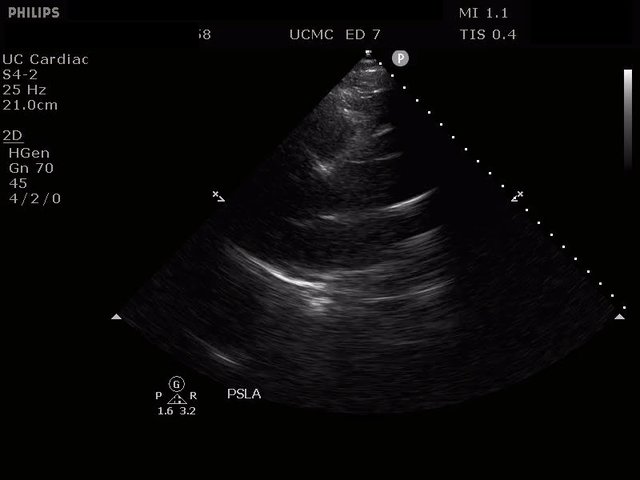

Parasternal short axis view with dissection flap visible in the descending thoracic aorta

The parasternal short axis view demonstrates evidence of a mobile hyperechoic structure within an anechoic tubular structure deep to the heart, which represents a dissection flap within the descending aorta. The parasternal long view demonstrates a dilated proximal aorta with a dissection flap originating at the aortic root. Aortic dissection is a challenging diagnosis to make, and the remainder of this article will discuss the bedside evaluation for aortic dissection with point of care ultrasound.